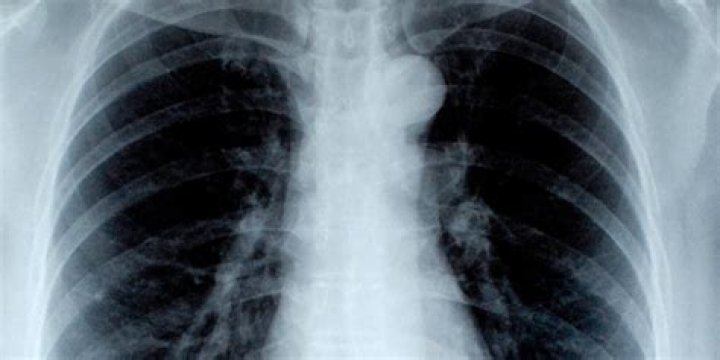

El traumatismo penetrante habitualmente es el resultado de la aplicación directa y abrupta de una fuerza mecánica sobre un área focal pequeña en la superficie externa del tórax, por lo general, con un proyectil, un arma blanca, objetos afilados, empalamiento (penetración de objetos) o fragmentos de explosiones, ya sean …

Un traumatismo de tórax es una lesión de gravedad que en muchos casos causa discapacidad o incluso la muerte. De hecho es, entre los diferentes traumas físicos, la principal causa de mortalidad tras los traumas a la cabeza y lesiones de la médula espinal.

Una herida abierta en el tórax succiona el aire del exterior, provocando un neumotórax con rápido desarrollo de insuficiencia respiratoria y con una gradual pérdida de sangre. Las lesiones del parénquima pulmonar y/o bronquial provocan neumotórax, que puede llegar a convertirse en neumotórax a tensión →cap.

Las heridas soplantes ponen de manifiesto la comunicación del espacio pleural con el exterior. En las heridas torácicas bajas, por debajo de la areola mamaria o la punta de la escápula posteriormente,el dolor abdominal puede indicar la penetración en el abdomen a través del diafragma.